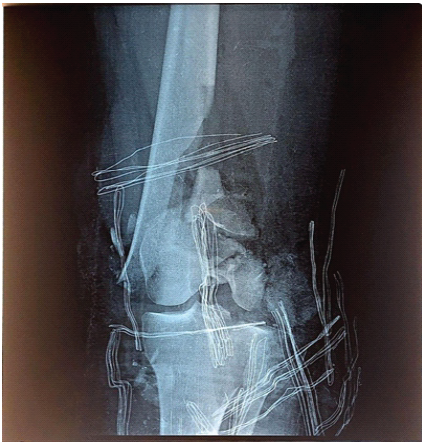

This patient is a 25-year-old female college student who was involved in a road traffic accident as a pedestrian struck by a motorcycle. She presented to the emergency department with a severe open fracture, with AO class: (AO 33-C3) (Fig. 1). The wound was a 15 cm laceration with exposed distal femur, patella, and lateral proximal tibial plateau.

Figure 1: Pre-operative anteroposterior and lateral radiographs showing a severely comminuted open distal femur fracture (AO/OTA 33-C3).

The distal 5 cm of the femur was severely comminuted. The preceding 10 cm showed a longitudinal split, with complete loss of the lateral aspect at the scene of the accident, while the medial aspect remained intact. Both femoral condyles were severely comminuted and no reconstrable.